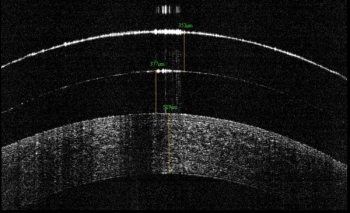

In the near future, eyecare providers will have devices that, given an image of a patient’s retina, can tell us the exact diagnosis at the touch of a button. AI will play an increasingly significant role in the way healthcare providers care for their patients in the clinic. There is real and imminent potential for earlier, more accurate, and more uniform diagnosis.